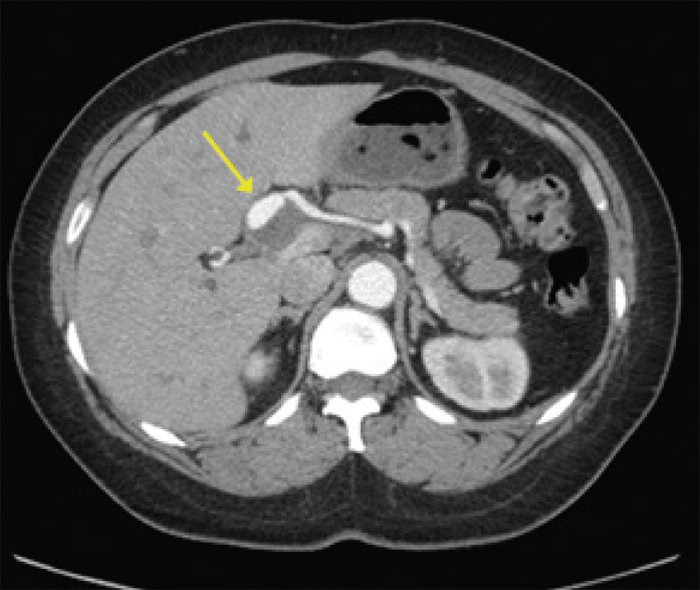

Completion angiogram demonstrated the coils in the HAA with preservation of flow in the distal right hepatic artery, maintaining blood flow to the right lobe of the liver (Figure 6). Following the procedure, the patient's symptoms resolved completely. LFTs remained normal throughout her stay. CT exam seven months after her procedure demonstrated the coil embolization in the previously present RHA aneurysm, and the patient remains asymptomatic 18 months later.